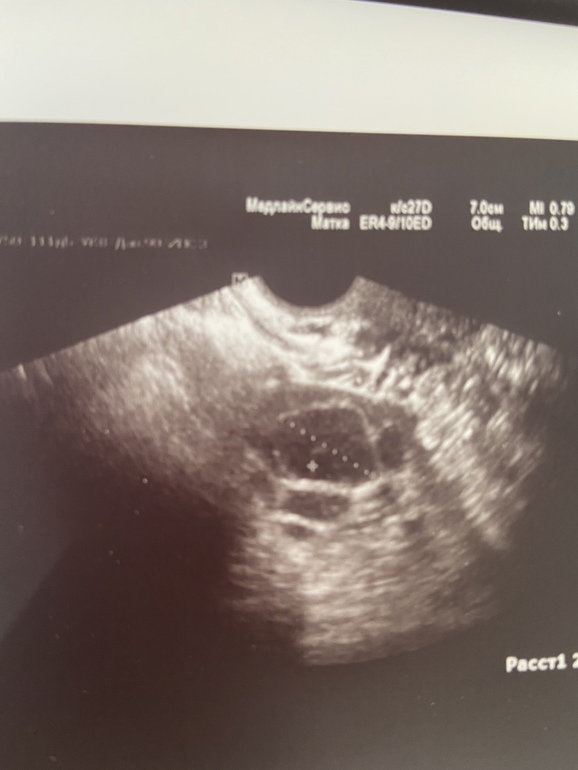

Вот фото

ФолликулометрияКололи хгч 5000ед на размере 21 мм